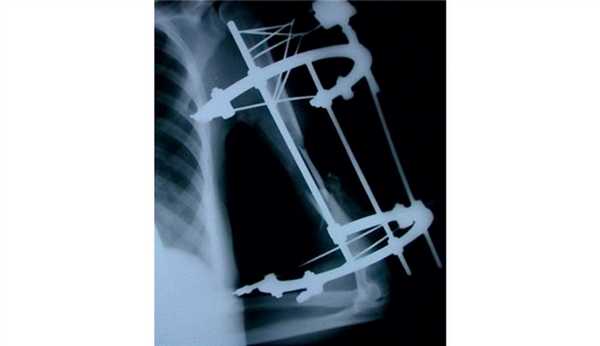

У 2 пациентов 3-й группы с хроническим остеомиелитом в стадии ремиссии выявлен ложный сустав плечевой кости. Им выполнена реконструктивная операция с применением ротированных надкостнично-кортикальных аутотрансплантатов для поддержки остеогенеза в условиях наружного чрескостного остеосинтеза по Илизарову.

В 5 наблюдениях при инфицированных ложных суставах и несросшихся переломах выполнены удаление металлоконструкций, некрэктомия концов костных фрагментов и наружный чрескостный остеосинтез по Илизарову. 3 пациентам операция дополнена пластикой костной раны фрагментами трехглавой (2) и плечелучевой (1) мышц.